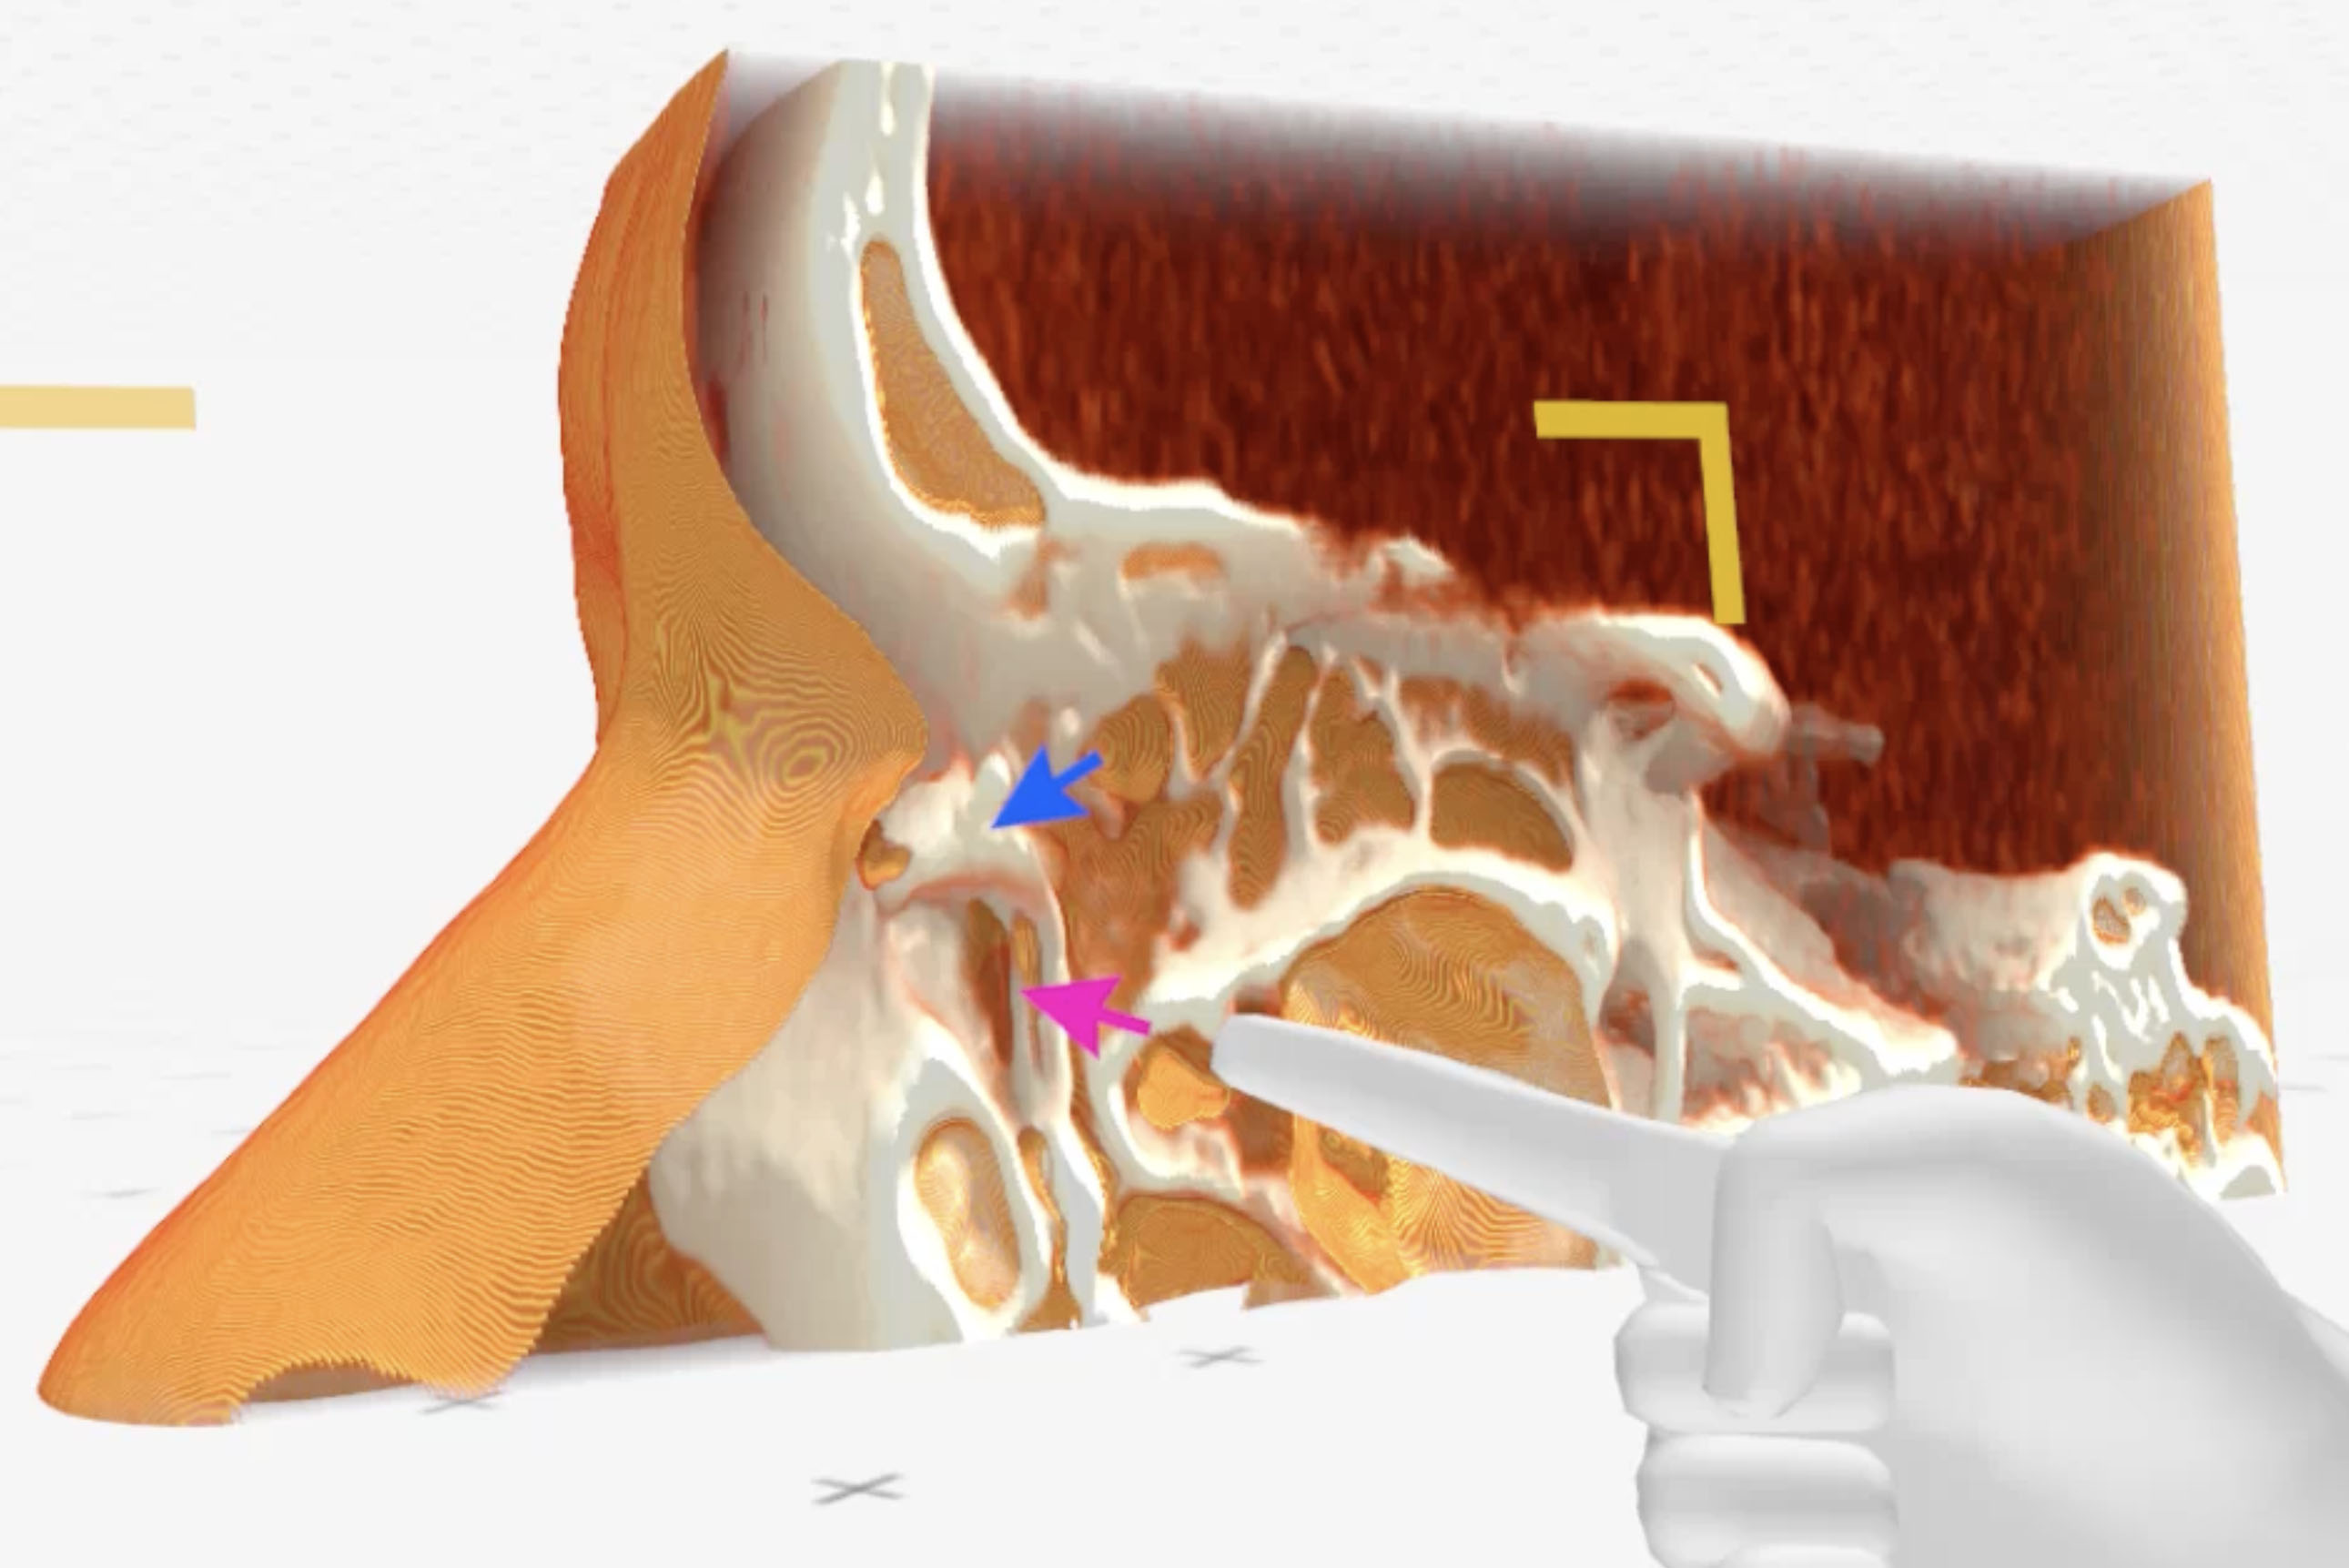

Medical Imaging XR (Medicalholodeck AG, Zurich, Switzerland) three-dimensional reconstructions obtained from CT-DCG DICOM files showed a well-defined lesion in the left lacrimal sac fossa, extending up to the beginning of the nasolacrimal canal (bony). The lacrimal sac appeared to be compressed against the posterior wall of the lacrimal fossa (Fig. 2-4).

Figure 2. Medical Imaging XR reconstruction shows contrast dye in the left lacrimal passages (blue arrow) and a space referring to a lesion compressing the lacrimal sac (pink arrow)